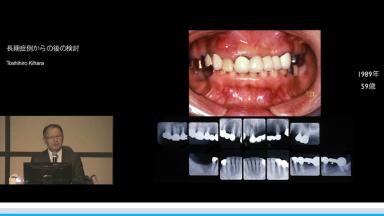

長期症例からの後の検討

インプラントの成功率は95%以上であるのに対し、日本では補綴歯の75%が無髄歯であるため、長期的にみると天然歯がなくなりインプラントが残る。その背景には、不適切な根管治療、補綴物による歯根破折が多いことがある。

欠損部隣在歯のトラブルフリー曲線でインプラントと天然歯、失活歯と生活歯を比較し、実際の症例を提示しながら最小限の治療で最大限の効果を得る方法が解説された。

インプラントが残るからこそ、最終設計が重要であり、患者の年齢や成功する要素を考慮して、1回目の治療時にもう一度大きく治療する必要のないようにするべきであり、その際に正常像の範囲内に入るよう治療を行うべきであると結論づけられていた。